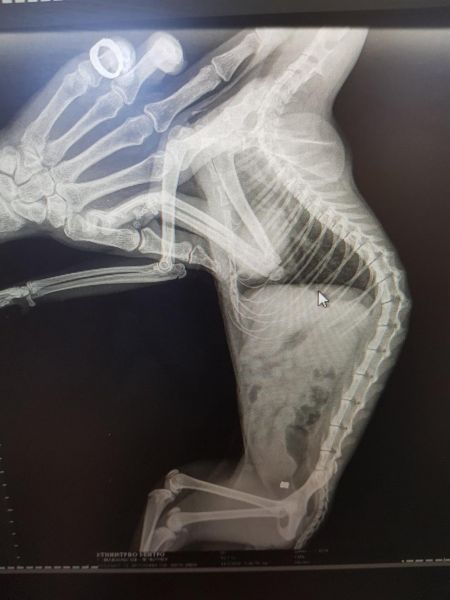

Άλλη μία περίπτωση βίας κατά ζώων έλαβε χώρα στο Ίππειος της Λέσβου, όταν πυροβόλησαν γατάκι που έσκισε σακούλα σκουπιδιών.

Όπως αναφέρει η Κιβωτός, ο δράστης, ο οποίος συνελήφθη είχε το θράσος να δηλώσει σε γνωστούς του ότι πυροβόλησε το γατάκι επειδή …έσκιζε τις σακούλες με τα σκουπίδια του.. «και έπρεπε να μάθει».